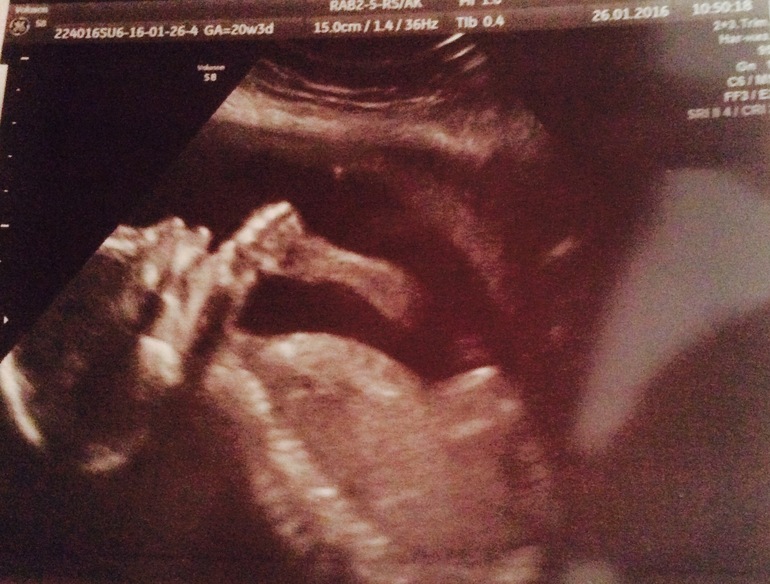

Всё о нашей беременностиИ снова здравствуйте мои дорогие девчули!!! Вот и прошёл мой 2ой скрининг😊 всё замечательно, малыш поначалу повернулся своей попкой и ни в какую не давался нам посмотреть его, мой хулигашка! Но всё же сдался нам))) лежал, открывал рот, показывал язык и сосал палец))) срок по УЗИ на 2 дня побольше акушерского, почти таки сровнялся! На сегодняшний момент нам 20 недель и 5 дней😊

А вот несколько фоток моего хулигашки🤗